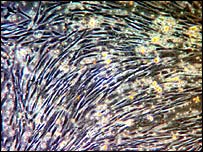

Uma pesquisa publicada na revista Nature Genetics mostrou que as células-tronco extraídas de embriões humanos são muito mais estáveis do que cientistas acreditavam. As células-tronco, que são células ainda sem diferenciação, têm segundo a ciência um potencial de curar doenças como câncer e mal de Parkinson ou males provocados por traumas, já que podem ser transformadas em qualquer tecido (e até órgãos) do corpo humano. Havia um certo medo de que os genes das células-tronco pudessem passar por mudanças que os tornaria instáveis para corrigir problemas quando as células fossem usadas em uma terapia. Mas cientistas da Universidade de Cambridge, na Grã-Bretanha, afirmam que essse temor não tem fundamento. Eles analisaram seis genes de quatro linhagens de células-tronco extraídas de embriões humanos. "O fato é que elas são mais estáveis do que, por exemplo, células semelhantes extraídas de camundongos, cujos genes sofrem alterações no decorrer do processo", disse Roger Pederson, chefe da pesquisa. Os cientistas avaliaram apenas células extraídas de embriões humanos descartados devido a abortos. Ainda não se sabe se embriões clonados se desenvolvem nas mesmas condições. Imprinting Os cientistas mostravam-se preocupados com fatores bioquímicos, que têm um papel fundamental em controlar a atividade genética da célula durante o seu desenvolvimento e diferenciação. Esses fatores asseguram, por exemplo, que a atividade dos genes seja balanceada à medida em que sua estrutura física vai mudando. Como herdamos duas cópias de cada gene, um de cada pai, há um perigo de que a combinação de alguns desses genes se torne, por exemplo, potente demais. Os fatores bioquímicos controlam o chamado imprinting (mistura) genético. Os cientistas tinham medo de que, uma vez manipuladas em laboratório, essas céulas não se desenvolvessem da forma correta, não crescendo ou crescendo demais - anulando um eventual tratamento. |